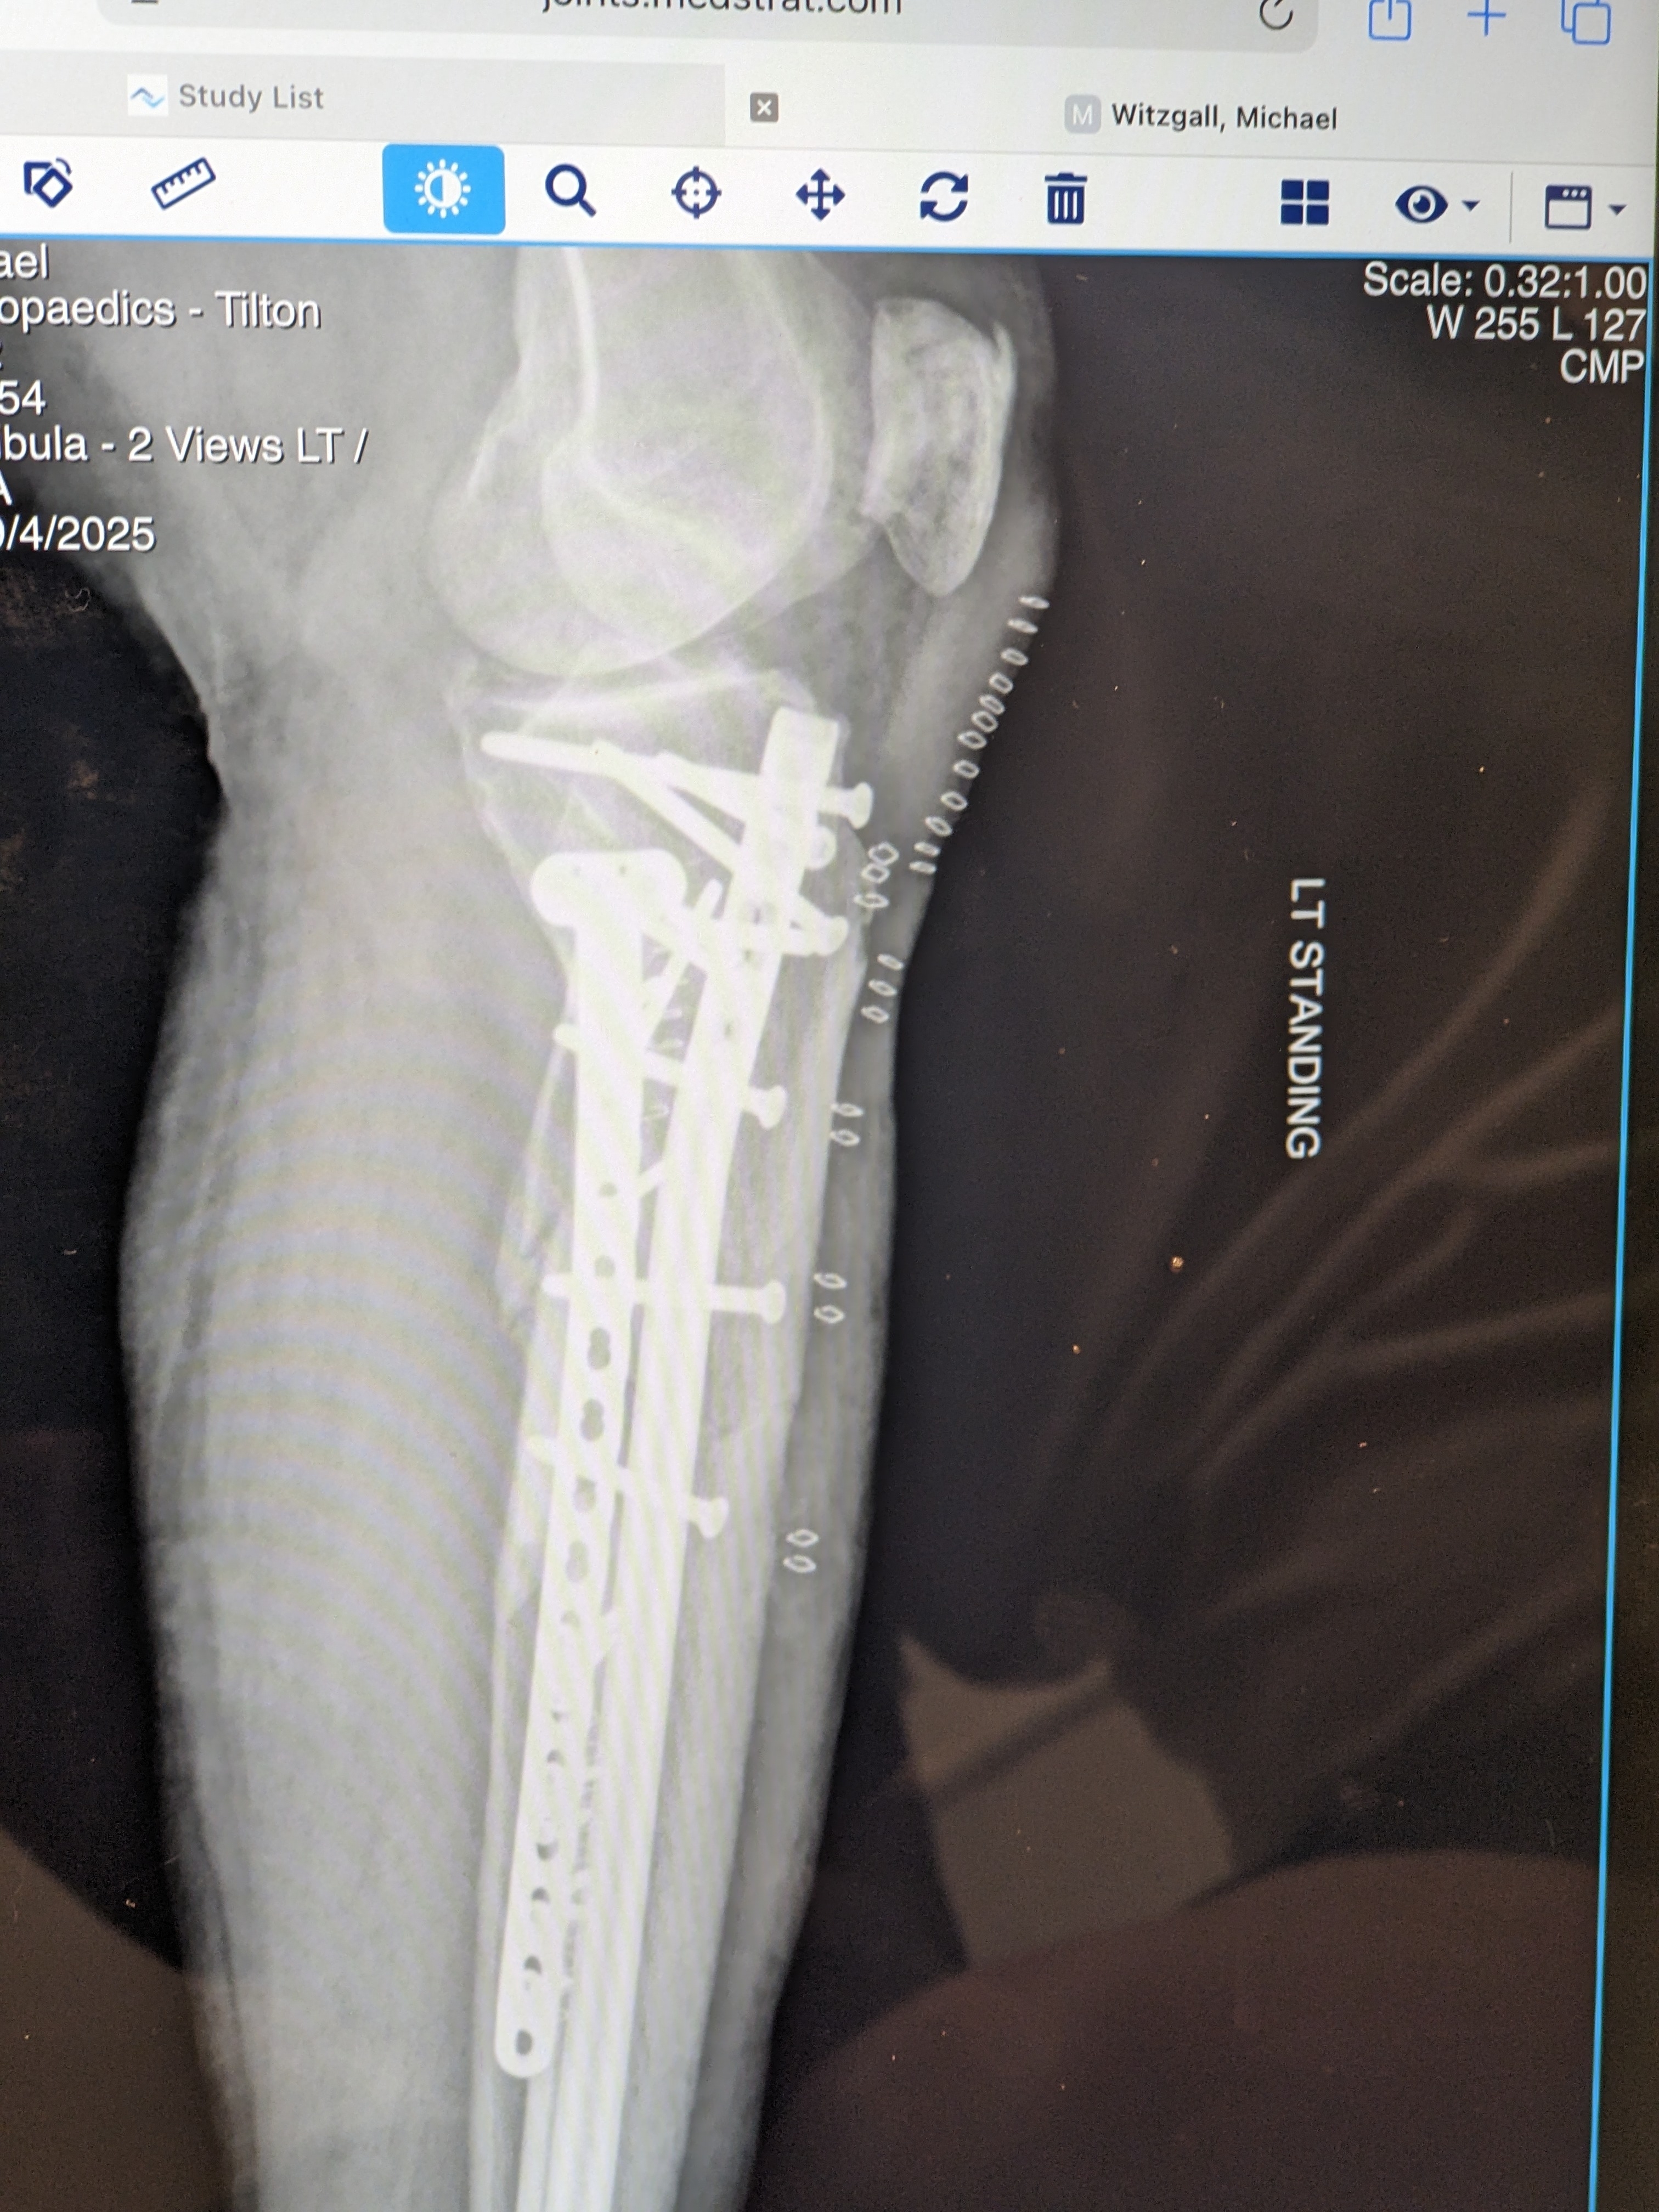

Wow. Looks like an Ace Hardware store.

I got my original hardware back that was removed and replaced with the Superduty stuff. I wonder if these items can be resold to third world regions in need of medical implants?

New hardware is providing more stability. Now only hope the crunched Tibia begins to mend.